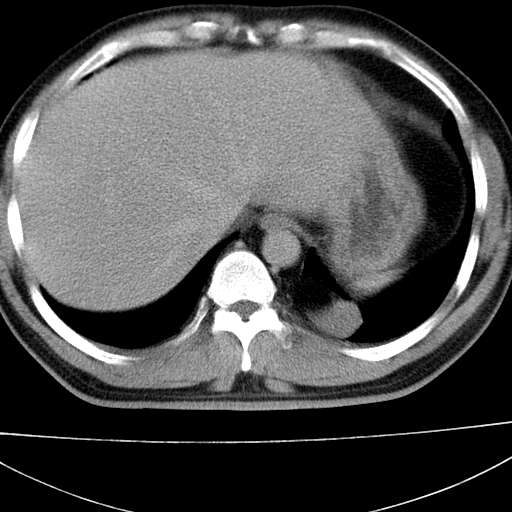

标题: CT21921:腹膜后腔肿物。患者男39Y。体检。增强扫描时间欠准 [打印本页]

标题: CT21921:腹膜后腔肿物。患者男39Y。体检。增强扫描时间欠准

左侧膈肌脚外缘见一结节样软组织影,密度较均匀,与胸膜关系稍密切,增强轻度强化;考虑来自胸膜良性病变(胸膜纤维瘤可能)。建议加扫胸部ct检查。

2、左下膈肌脚外缘结节状病变,与胸膜交界面呈锐角,胸膜下脂肪线可见,定位于肺内,考虑支气管囊肿或肺隔离征可能性大。

左膈肌角后腹膜腔见肿物影,其内见脂肪密度灶及软组织密度灶,强化不明显。病灶大部在后腹膜内。考虑异位嗜铬细胞瘤或脂肪肉瘤、畸胎瘤